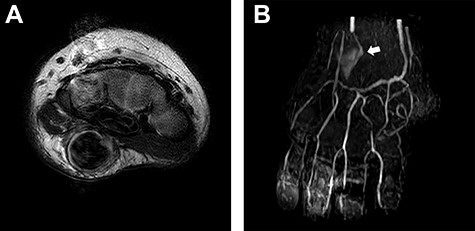

An 8-month-old infant was referred our department for a mass on her right hand. She had an episode of falling from her bed. Before that, parents did not realize any abnormality of her hand. A dull rise with thrill was observed on the hypothenar eminence. Tenderness and neuro-radiating pain was not evident, highly possibly because of her age. She did not present any other disorder. No bone fracture was observed. Ultrasonography revealed arterial blood flow inside. Contrast-enhanced magnetic resonance imaging (MRI) illustrated a bulge of artery in her hypothenar part (Fig. 1). An ulnar artery aneurysm was suspected. Blood route continuity from the radial artery to both deep and superficial palmar arches was confirmed.

Presurgical images. (A) MRI revealed existence of a subcutaneous mass with the size of 9 x 9x 17 mm. (B) MR angiogram showed that the ulnar artery flow was reduced and deviated at the mass (white arrow). Continuity of the arterial network from the radial artery to the fingers was confirmed.